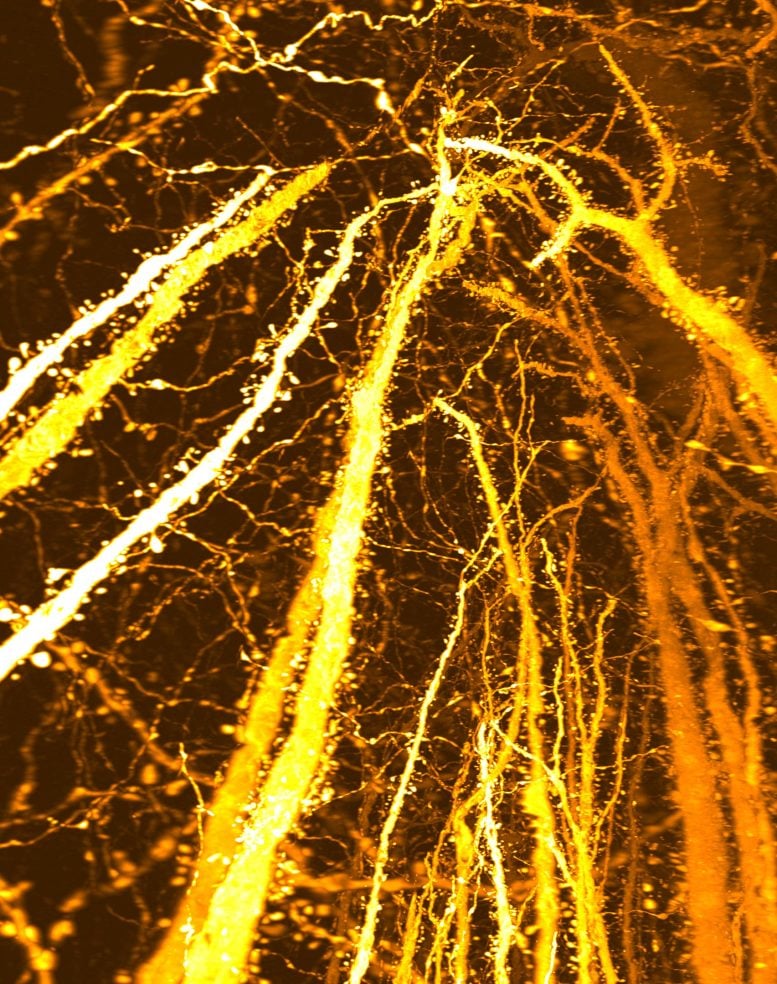

This image shows densely accumulated dendritic spines. Researchers from Kyushu University discovered a previously unrecognized synaptic “hotspot” that forms during adolescence, challenging the long-held view that adolescent brain development is driven mainly by synaptic pruning. Credit: Takeshi Imai / Kyushu University

A research team at Kyushu University is now pushing back on this long-held idea that adolescence is mainly about cutting connections. In a study published in Science Advances, the group reports that the adolescent brain is also building something new: dense, tightly packed clusters of synapses that appear on specific stretches of dendrites, the branching extensions of neurons.

“We did not set out to study brain disorders,” says Professor Takeshi Imai at Kyushu University’s Faculty of Medical Sciences. “After developing a high-resolution tool for synaptic analysis in 2016, we looked at the mouse cerebral cortex out of curiosity. Beyond seeing the beauty of the neuronal structure, we were surprised to discover a previously unknown high-density hotspot of dendritic spines, the tiny protrusions in dendrites where excitatory synapses are formed.”

Using this method, the team created a complete map of dendritic spines across individual Layer 5 neurons. Their analysis uncovered an unexpected region of extremely high spine density located along the apical dendrite. Further comparisons across developmental stages showed that this dense cluster does not appear early in life but instead emerges specifically during adolescence.

To determine how and when this dense region forms, the researchers followed changes in dendritic spine distribution over time. In mice that were two weeks old and had not yet been weaned, spines were spread fairly evenly along the dendrites. However, between three and eight weeks of age, a period that spans early development through adolescence, spine numbers increased sharply in one specific section of the apical dendrite. Over time, this selective growth led to the formation of a concentrated synaptic hotspot.